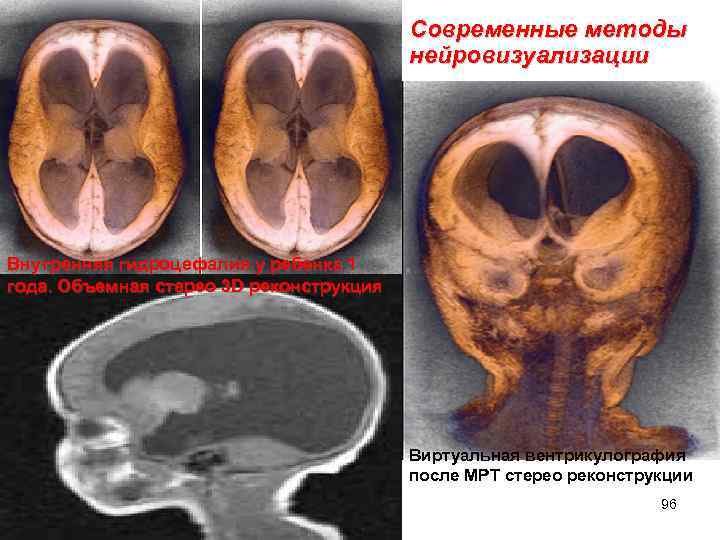

Современные методы нейровизуализации Внутренняя гидроцефалия у ребенка 1 года. Объемная стерео 3 D реконструкция Виртуальная вентрикулография после МРТ стерео реконструкции 96